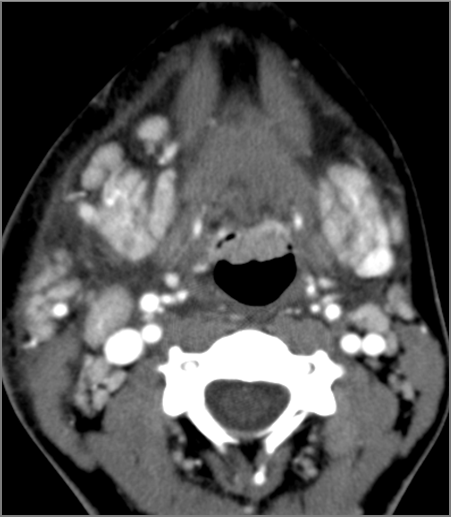

9 month old male presenting to the emergency room with poor feeding, fever, respiratory distress and possible retropharyngeal abscess or suppurative retropharyngeal adenitis.Exam

There is excessive enhancement or thickening of the mucosa or hypertrophy of the palatine or lingual tonsillar tissue or the lymphoid tissue along the glossotonsillar sulci and posterior pharyngeal wall. |

Yes | NA |

There is reactive retropharyngeal lymphadenopathy. |

There is suppurative retropharyngeal lymphadenopathy. |

If there is suppurative retropharyngeal adenopathy what is the maximum short axis dimension of the largest suppurative node. Measurement |

< 2cm | NA |

There is edema/abscess within the adjacent parapharyngeal and retropharyngeal spaces. |

Pharyngitis with suppurative retropharyngeal adenitis.